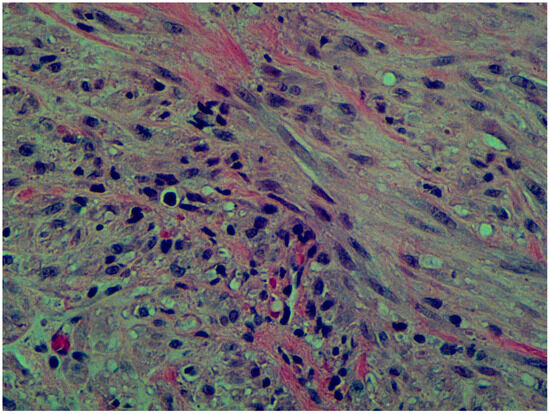

2. Case Presentation